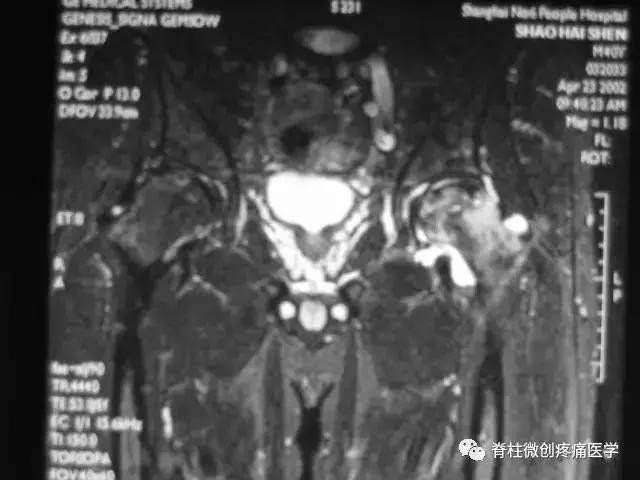

正常成人股骨头的MRI表现正常成人股骨头骨髓内富含脂肪,在T1及T2加权图像上成圆形的高信号。股骨头及股骨颈表面骨皮质均为低信号。

在冠状面上,股骨头中央的承重骨小梁,表现为自外下缘到内上缘的稍低信号带。闭合的骨骺线为横行低信号线,两端与致密骨相连。

典型的MRI表现为股骨头前上部负重区在T1W上显示线样低信号区,T2W上显示为局限性信号升高或“双线征”。

在MRI上出现“双线征”,这是股骨头缺血坏死的特异性MRI表现之一。

在T1W上,股骨头前上部负重区,有硬化缘围绕较低、不均匀信号的新月形坏死区。

在T2W上,病灶为星月形高信号区。